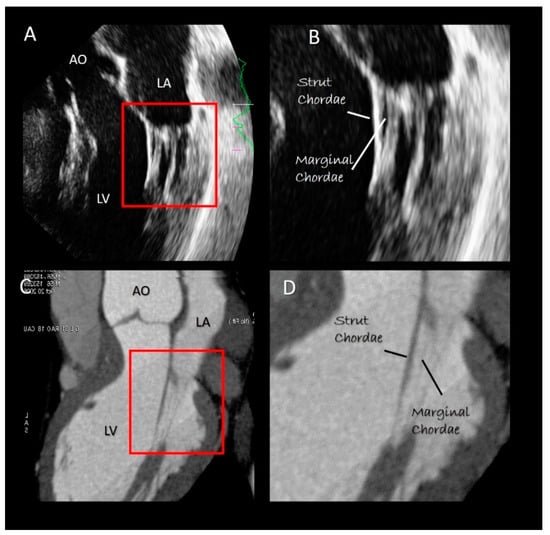

Both 2D TTE/TEE echocardiography and CT may visualize the chordal apparatus. However, being cross-sectional modalities, moving chordae can be visualized only when segments of them pass through the tomographic plane (Figure 7). Theoretically, 3D TTE/TEE should be the best method for visualizing the chordal apparatus, since chordae remain within the pyramidal data set during the cardiac cycle. However, the spatial resolution of 3D TTE/TEE is poor in comparison with 2D TTE/TE. Moreover, because of the blurred artefacts, thin structures such as chordae tendineae appear thicker than they actually are [25].

Figure 7.

(A) 2D TTE and (C) CT cross section in long-axis view. (B,D) Magnified images of the structures inside the red rectangle of panel A and C, respectively, showing the strut and marginal chordae (see text).